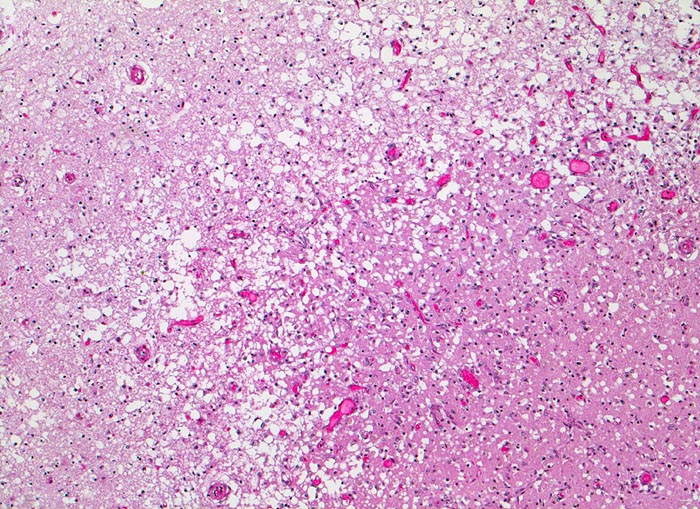

anämischer Hirninfarkt

vaskulär / Durchblutungsstörung

Hirn parietal

Randbereich des Infarktes mit spongiotischer Auflockerung des Hirnparenchyms, Gefässneubildungen und unscharfer Mark-Rinden Grenze. In der helleren Rinde links im Bild sind keine Neuronen sichtbar.

Vor 7 Tagen Entwicklung eines Hemisyndrom links.

50